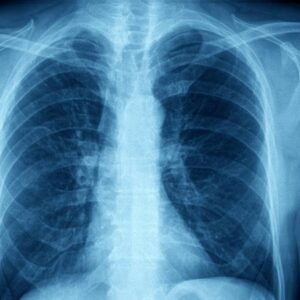

Possible Complications of Asthma

Asthma is a condition that affects an estimated 300 million people across the globe. There are a number of complications that can arise for asthma patients. Some of these include- Increased risk of infections such as pneumonia or influenza. Decreased quality of life due to poor management of the condition.